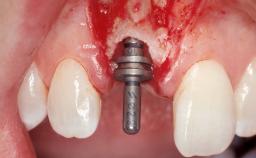

Immediate Placement of an Implant in a Maxillary Left Central Incisor Site

A 33-year-old female patient presented with an upper left central incisor that required extraction after a failed endodontic therapy. The tooth had been traumatized when the patient was a teenager and had undergone several endodontic treatments, including two apicectomy procedures. The patient was in good health and did not smoke. Clinical examination showed that the patient had a high lip line. In full smile, the gingival margins of the upper teeth were visible to the first molars. The gingival margins of central incisors 11 and 21 were only just showing. Examination of tooth 21 confirmed that the tooth was mobile and had hypererupted by 1 mm.